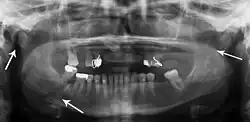

Panoramic radiography

Panoramic radiographs are tomograms where the mandible is in the focal trough and show a flat image of the mandible. Because the curve of the mandible appears in a 2-dimensional image, fractures are easier to spot leading to an accuracy similar to CT except in the condyle region. In addition, broken, missing or malaligned teeth can often be appreciated on a panoramic image which is frequently lost in plain films. Medial/lateral displacement of the fracture segments and especially the condyle are difficult to gauge so the view is sometimes augmented with plain film radiography or computed tomography for more complex mandible fractures.

Panoramic radiograph of a simple mandible fracture of the right mandibular body, minimally displaced. Note that the teeth to the left of the fracture do not touch -